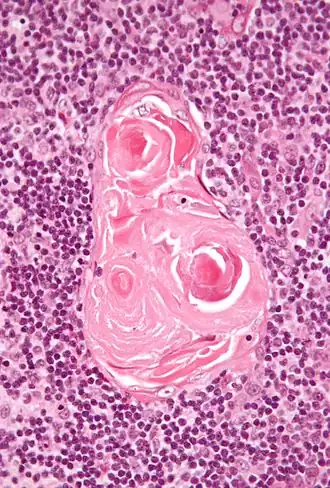

Micrographie des corpuscules de Hassal

Les corpuscules de Hassal, appelés aussi corpuscules thymiques, sont des structures arrondies, éosinophiles, lamellaires et en bulbe d’oignon situées dans la zone médullaire du thymus de l'homme. D'origine endodermique, ces structures épithéliales doivent leur nom au médecin britannique Arthur Hill Hassall (en) qui les a découvertes en 1846[1].

Leur fonction reste encore obscure mais il semble qu'ils peuvent, grâce à la production de la cytokine TSLP (thymic stromal lymphopoietin), intervenir dans le processus inflammatoire.